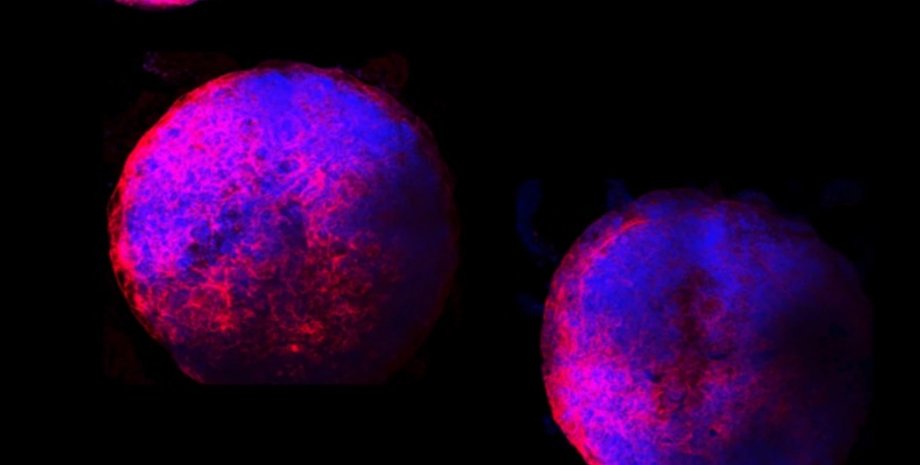

Фото: Michigan State University

К шестому дню миниатюрные сердца начали биться, а к пятнадцатому – превратились в сферы шириной около 1 мм.

Команда говорит, что выращенные в лаборатории мини-сердца подробно показывают, как развивается плод человеческого сердца. К шестому дню органоиды начали биться, а к 15 дню они превратились в сферы шириной около 1 мм со сложными внутренними камерами. Они также содержали все основные типы сердечных клеток.